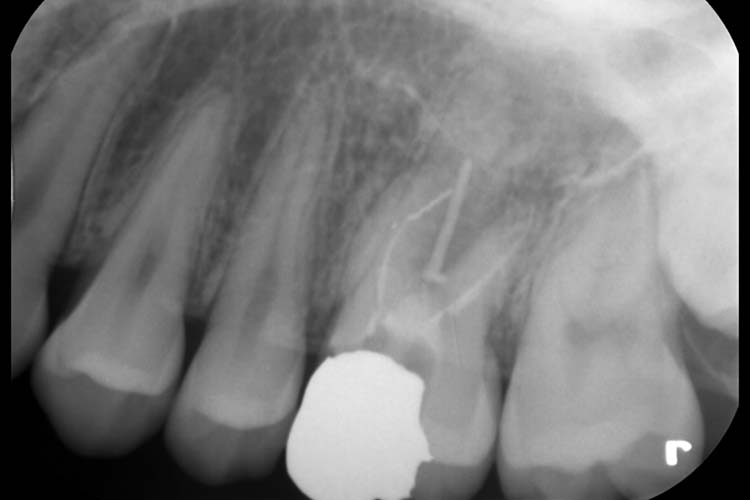

症例3

BEFORE

AFTER

| 患者 | 50代 女性 |

|---|---|

| 主訴 | 左上奥歯が噛むと違和感がある。 |

| 治療期間 | 4~5回程度 |

| 治療費 | 精密根管治療(保険診療) 仮歯作成の場合3,000〜5,000円 |

| 治療内容 | 左上6番近心頬側第二根管の見逃しによる再感染のため、マイクロスコープ下にて根管治療を行った。 |

| 治療のリスク | 治療直後〜3日程度、鈍痛や腫れを生じる場合がございます。 |

詳細を見る